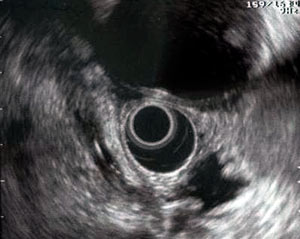

Ecoendoscopia